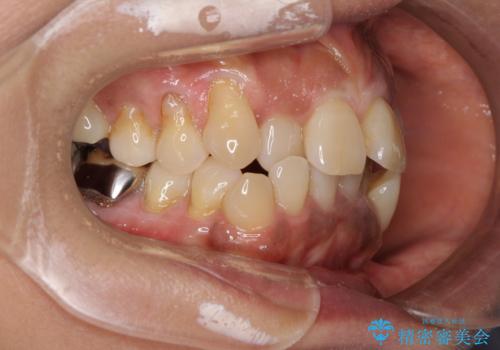

- 八重歯やクロスバイトを気にして来院された患者様です。

口元の突出感はありませんでしたが、デコボコが強く、非抜歯矯正とすると出っ歯仕上がりとなる可能性があったため、上下左右の第一小臼歯4本を抜歯し、ワイヤー装置にて矯正治療を行うこととしました。